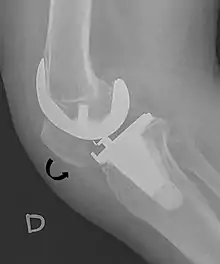

Patella baja.[4]

A patella alta is a high-riding (superiorly aligned) patella. An attenuated patella alta is an unusually small patella that develops out of and above the joint.

A patella baja is a low-riding patella. A long-standing patella baja may result in extensor dysfunction.[5]

Insall-Salvati ratio (A divided by B).[6]

The Insall-Salvati ratio helps to indicate patella baja on lateral X-rays, and is calculated as the patellar tendon length divided by the patellar bone length. An Insall-Salvati ratio of < 0.8 indicates patella baja.[6]